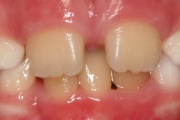

Puudub ülemine tsentraalne intsisiiv, kuid külgmised lõikehambad on juba lõikunud.